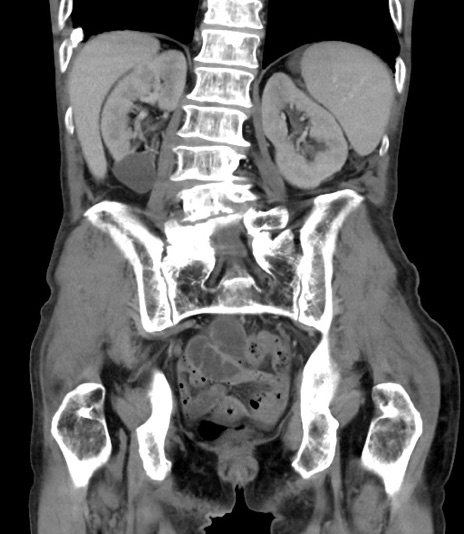

症例3(冠状断像)

【症例】 70歳代男性

【主訴】右鼠径部腫瘤、疼痛

【現病歴】本日朝より上記主訴あり、受診。

【既往歴】膀胱癌にて膀胱全摘、両側尿管皮膚瘻

【データ】WBC 5600、CRP 0.56